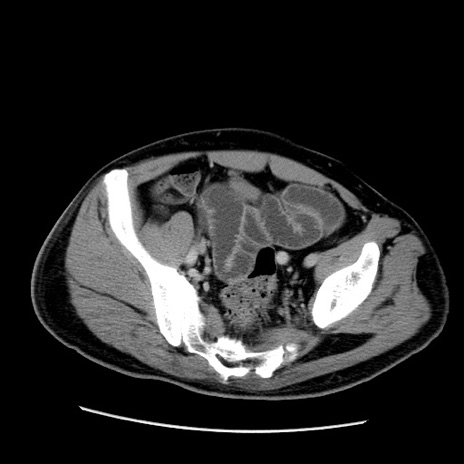

症例22(横断像)

【症例】50歳代男性

【主訴】腹痛

【現病歴】AVMからの被殻出血のため回復期リハ病棟入院中。 本日午後3時頃急に下腹部痛が出現した。

【既往歴】AVM、被殻出血、虫垂炎、高血圧

【身体所見】意識晴明、左半身不全麻痺、会話の理解は良好、36.5°C、腹部:膨隆、全体に板状硬、下腹部正中に圧痛点あり、反跳痛-、筋性防御不明、右下腹部にope scar

【データ】WBC 9400、CRP 0.06